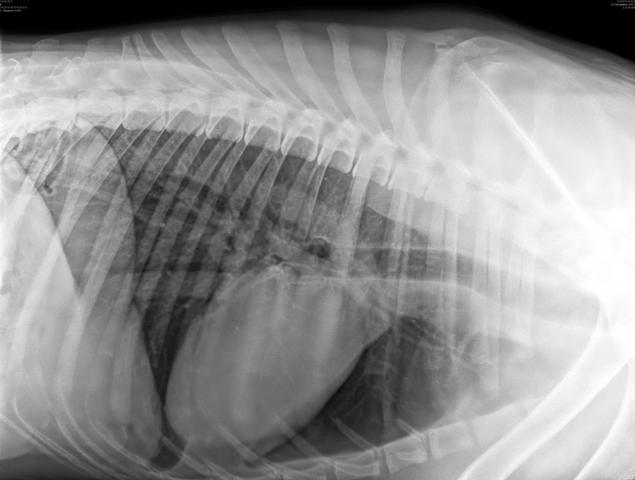

Мы делали комплексное УЗИ, оно есть в фотоархиве. И вот тут я прикрепляю. Плюс отдельно делали УЗИ сердца, почек, мочевого. Веде норма или почти норма.